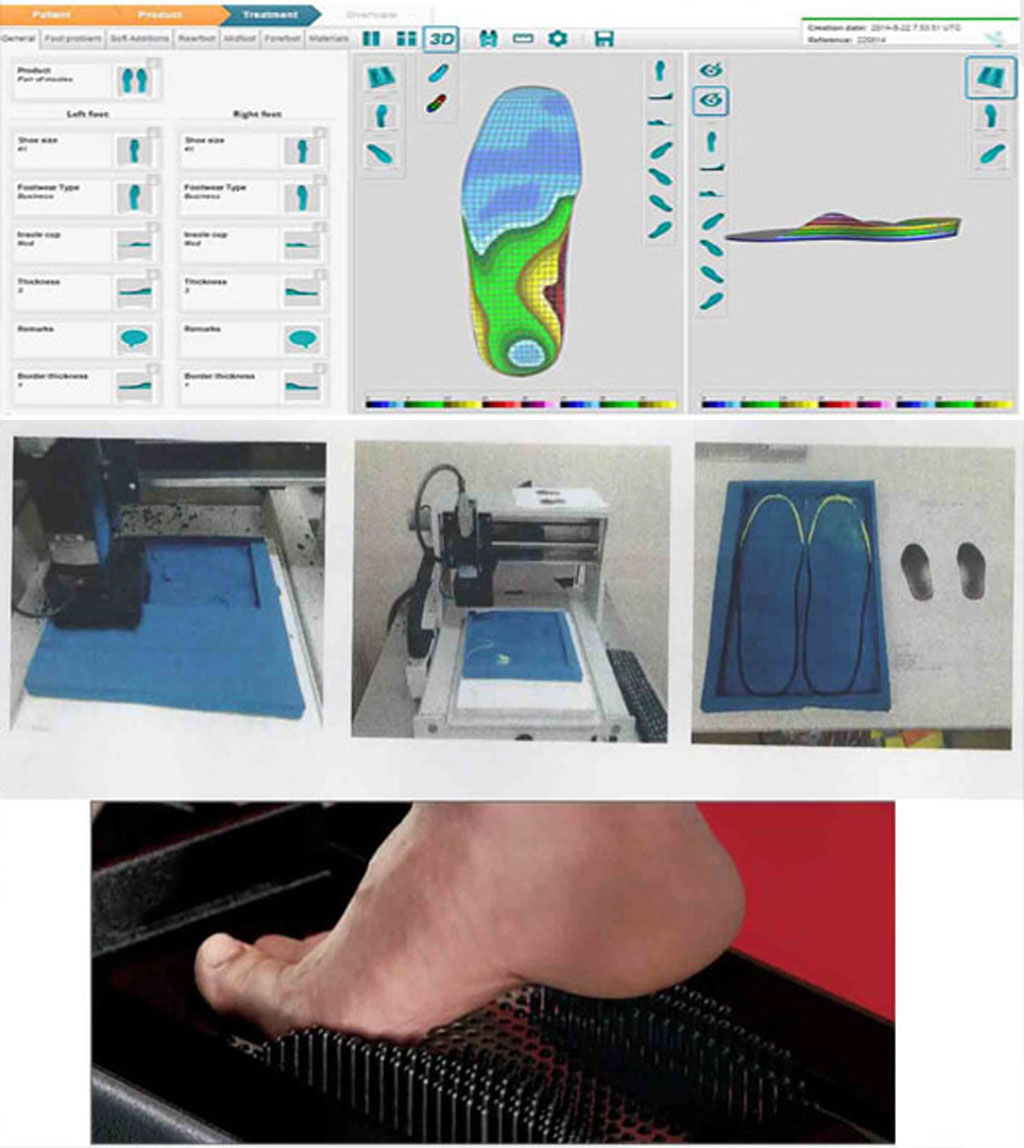

2. CNC ile Üretim

Analiz verileri özel yazılıma aktarılır ve CNC Router ile milimetrik hassasiyette tabanlığınız üretilir. Her tabanlık %100 size özeldir.

- Mikron hassasiyetinde işleme

- 3 eksenli CNC Router

- Hızlı üretim süreci

- Tekrarlanabilir kalite